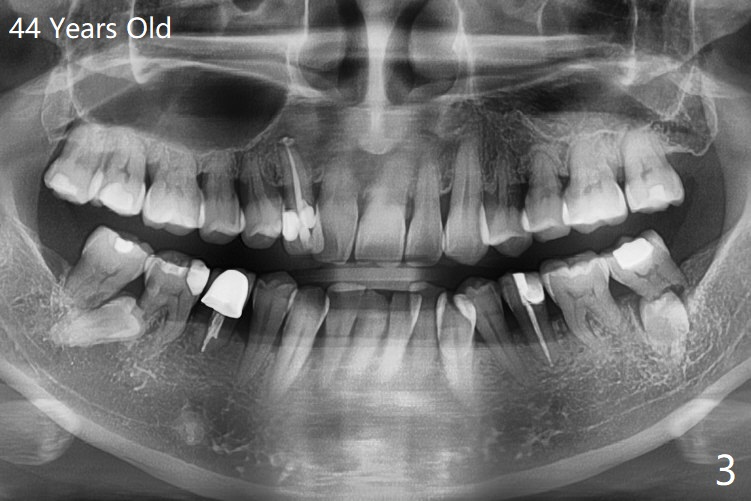

A 34-year-old woman has 2 supernumerary lower 2nd premolars located between the 1st and 2nd molars (Fig.1,2). Ten years later, the lower left 2nd molar has mobility associated with root resorption (Fig.3).